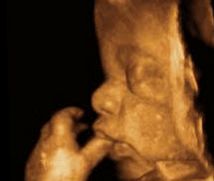

• -郑州万安妇产医院

相册

HS 上传于 18-10-29 | 报错